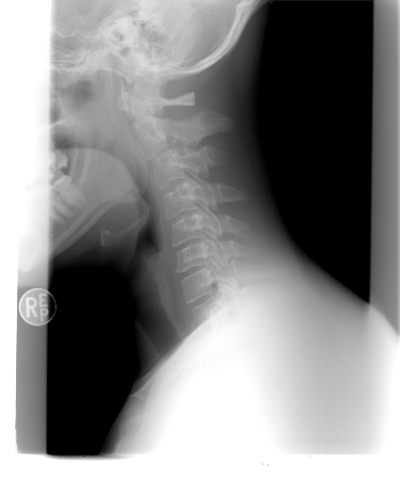

목이 앞으로 빠진채 목뼈가 펴져있는 엑스레이 사진